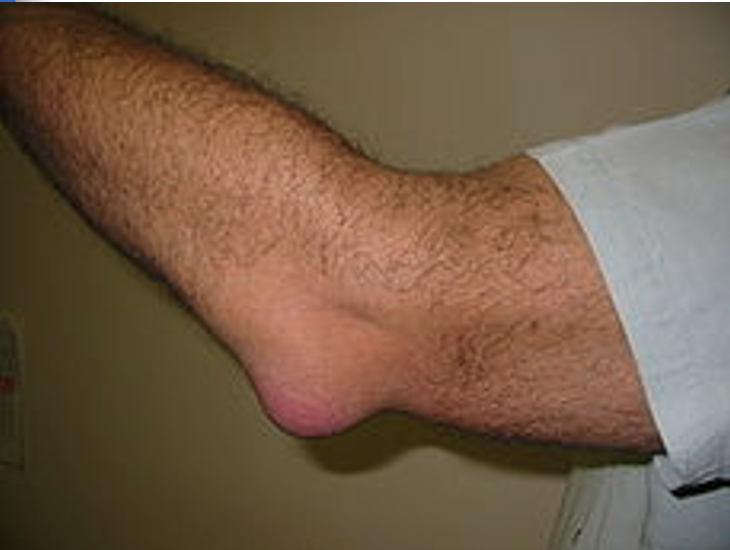

Elysia was the star tennis player on both her high school and college team. Eventually the cusions of her elbow joint became extremely swollen and painful. Elysia has...

bursitis